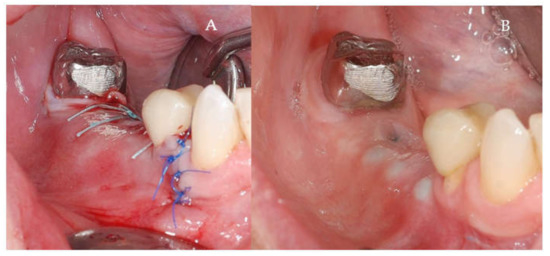

Clinical and CBCT aspects of patient from the test group, describing the stages of S-GBR technique and implant-prosthetic stage, are presented in Figure 1, Figure 2, Figure 3, Figure 4, Figure 5, Figure 6, Figure 7, Figure 8, Figure 9, Figure 10 and Figure 11. CBCT exam allows the evaluation of the horizontal alveolar bone defect and the position of the mandibular alveolar nerf (Figure 1A,B). Figure 1C,D show cross-sectional CBCT aspects of the implant sites. Figure 2 shows the narrowed mandibular alveolar bone with horizontal resorption. Figure 3 shows the exposed buccal surface of the alveolar ridge with severe horizontal resorption, after flap opening. The inserted implants (4.5 mm diameter, 11.5 mm length) and osteosynthesis screws (45° from the occlusal plan) are shown in Figure 4A. The placement of graft (autologous bone and xenograft) and collagen membrane is shown in Figure 4B. Figure 5A shows tension-free sutures, due to periosteal incisions alveolar ridge. Figure 5B shows clinical aspect at 7 months after surgery, with gingival tissue adherent on the reconstructed alveolar ridge. Figure 6 shows OPG aspect at follow-up of 7 months, with osseointegration of the dental implants. Figure 7A shows clinical aspect before osteosynthesis screws removal. Figure 7B shows clinical aspect after osteosynthesis screws removal. Figure 8A shows healthy peri-implant soft tissues. Figure 8B shows repositioning key for perfect position of abutments. Figure 10A,B show clinical aspects of implant-supported prosthetic restoration. Figure 11A,B show CBCT aspects of Osseo integrated dental implants at 24 months follow-up.

Figure 5.

(A,B) Follow-up of the S-GBR surgery. (A) Tension-free sutures. (B) Clinical aspect at 7 months post-surgery.